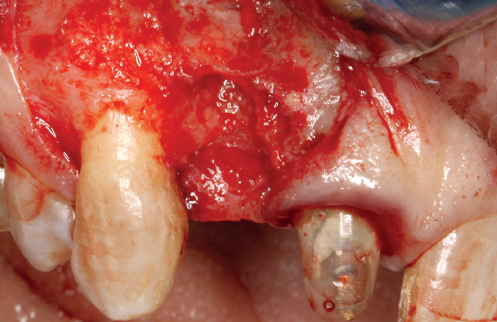

(Figuras 5 y 6). Con esta imagen se procede a la apertura de un colgajo y la explantación del implante. Se retira también la corona situada en el diente 1.1 para poder realizar otra corona que servirá para apoyar el provisional en extensión para la zona del 1.2, mientras cicatriza la primera intervención. En este primer abordaje se coloca también un injerto en bloque obtenido de la rama mandibular que se fija con un microtornillo en la zona a regenerar donde se ha perdido la cortical vestibular. Una vez fijado y posicionado, se rellena alrededor del injerto en bloque con hueso particulado obtenido con un bone-scraper de la misma zona donante embebido en PRGF-Endoret para una mejor fijación y viabilidad celular (Figuras 7-9).